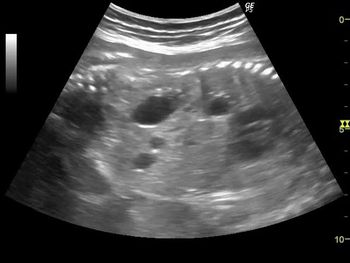

Challenge your diagnostic skills with this image quiz: Is this ovarian lesion cystic in nature or something else?